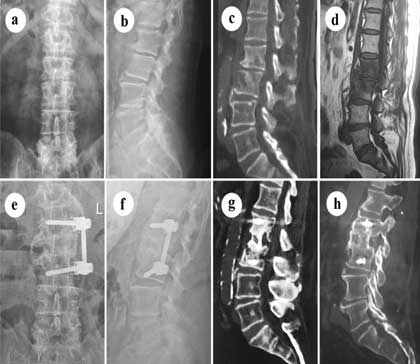

Instrumented posterior lumbar interbody fusion (iPLIF) is a common spinal fusion surgical technique for addressing low back pain resulting from degenerative lumbar spine disorders. It involves fusion of two or more levels utilizing screws, rods, and an interbody graft.

It has a theoretical advantage over instrumented posterolateral fusion (iPLF) in that it provides better support for the vertebra along with several potential neurological benefits, but as of 2011 evidence demonstrating actual improved clinical outcomes was lacking.

TLIF surgery, or transforaminal lumbar interbody fusion, is an approach to spinal fusion surgery in which the neurosurgeon accesses the lower spine through the intervertebral foramen. The intervertebral foramen is the opening between the bones of the spine, called vertebrae, through which nerves leave the spinal cord and en route to other parts of the body.

TLIF is one of several different approaches to spinal fusion surgery. Spinal fusion is performed to join together two or more spinal vertebrae, eliminating movement between them. This is done by removing the intervertebral disc between the two vertebrae, which normally enables the spine to bend and rotate, and inserting a bone graft in its place. The bone graft heals over several months, fusing the vertebrae together and stabilizing the spine.